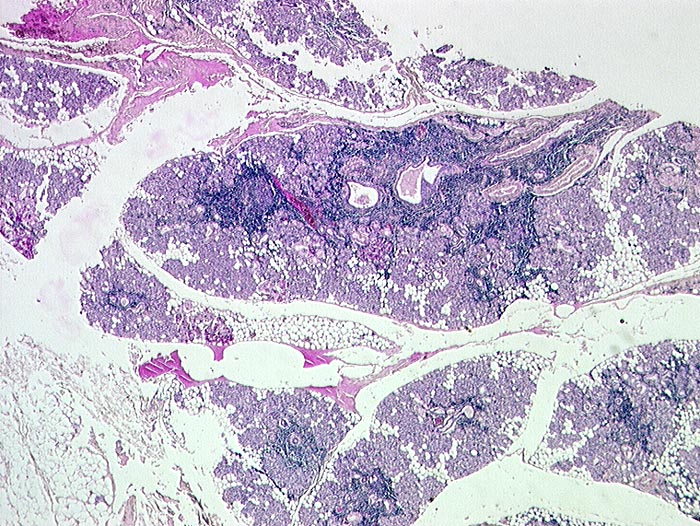

Autoimmun- Sialadenitis bei Sjögren Syndrom

Parotis

Das Zellbild ist je nach Stadium mehr oder weniger zellreich und zusammengesetzt aus Lymphozyten, Myoepithelien und selten Azinuszellen. Ein lymphozytäres Zellbild ist in Kombination mit dem typischen klinischen Bild (Keratokonjunktivitis sicca, Xerostomie, rheumatische Erkrankung) für die Sicherung der Diagnose ausreichend. Auf die Lippenbiopsie kann in diesem Fall verzichtet werden.